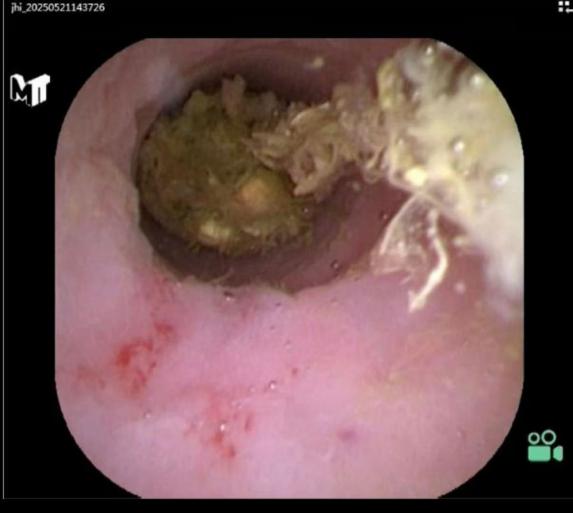

找到开口后,将一根更细的阑尾子镜通过结肠镜的活检孔道插入阑尾腔内。

阑尾子镜清晰显示阑尾内部结构、炎症程度以及是否存在罪魁祸首——粪石。

内镜下阑尾取粪石术:如果灌洗无法冲出较大或嵌顿牢固的粪石,医生会使用内镜器械(如取石网篮、取石球囊),直接伸入阑尾腔内,精准抓取或套取粪石,从阑尾管腔取出,彻底解除梗阻。